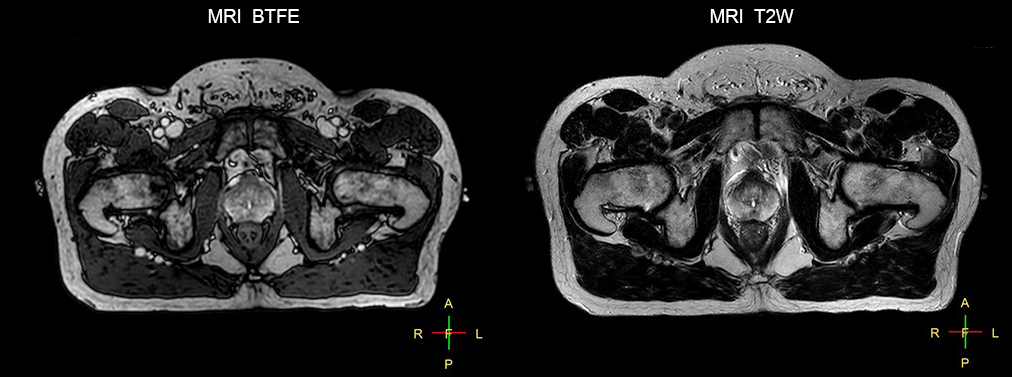

The potential benefits of using MR in radiation therapy planning are obvious: with its excellent soft tissue contrast, MR images can help to define lesions for well-targeted radiation therapy (RT) planning. During treatment, MR can visualize changes in patient anatomy and tumor biology to help adapt the treatment plan to these changes. Post-treatment MRI is used to monitor treatment response.

“The main reason to integrate MR imaging in RT planning is the superb soft tissue contrast that allows detailed delineation of tumors and healthy organs, which is crucial for RT planning,” says Craig W. Stevens MD, PhD.

“The good visualization is why a lot of cancer treatments can benefit from MR based treatment planning, because if we can localize a tumor better, we can aim the radiation beam at it better. This potentially allows us to shrink our margins and spare more healthy tissue.”

“The biggest problem for CT-based planning, especially in prostate, is you can’t see the cancer very well,” says Dr. Stevens. “On CT it can be quite challenging to see the edge of the prostate especially at the apex. When the edge of the prostate can’t be delineated well on CT, radiation oncologists will increase their margins a little bit so they don’t miss it, but that can also increase toxicity.”

“Using MR, the prostate is well delineated. We quickly see the edges of cancerous tumors like in prostate cancer, and as normal structures can be defined, we can optimize the treatment plan to protect these organs and their normal function. This can potentially improve the outcome. And it improves workflow as well. We can contour more quickly, confident that the tumor is going to be in the field.”

“The Ingenia 3.0T MR scanner provides high resolution allowing us to make scans fast for the patients. It also gives the potential to include methods like MR spectroscopy and diffusion weighted Imaging, which we’re in the process of doing right now,” Dr. Stevens adds.